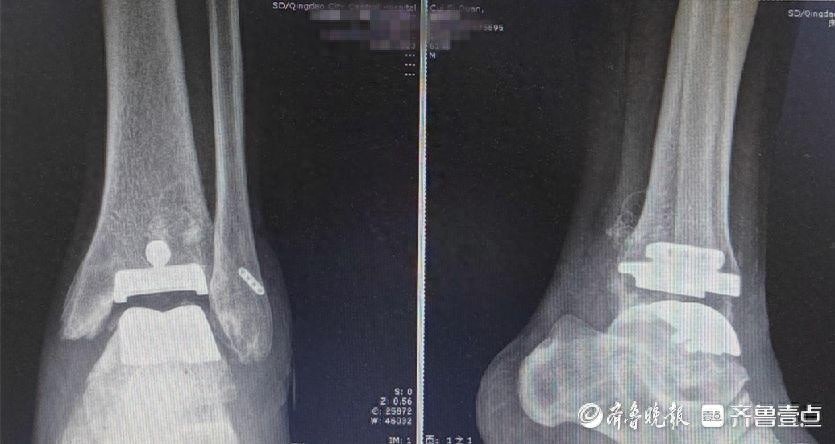

会议期间,与会者参与了关节与骨质疏松诊疗技术的专项培训,并进行了病例的深入讨论,这些活动构成了会议的核心内容。通过技术培训,参会者的诊疗技能得到了显著提升;而病例讨论环节,则促进了不同经验背景的专家之间的观点交流,实现了共同进步。